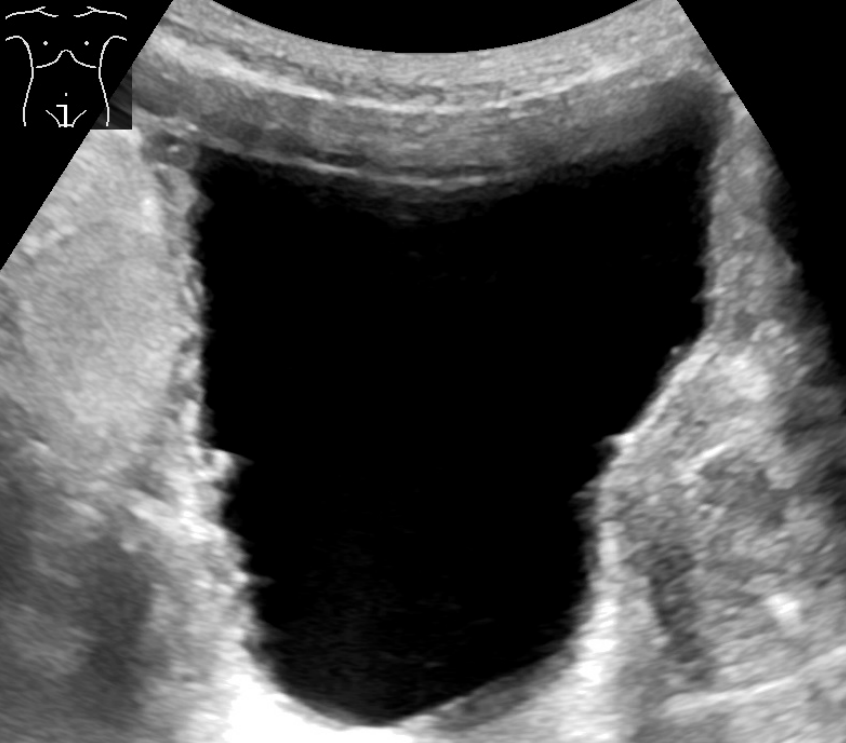

The body stores urine — water and wastes removed by the kidneys — in the urinary bladder, a balloon-like organ. The bladder connects to the urethra, the tube through which urine leaves the body.[10]

Urination, or voiding, is a complex activity. The bladder is a balloon-like muscle that lies in the lowest part of the abdomen. The bladder stores urine then releases it through the urethra, the canal that carries urine to the outside of the body. Controlling this activity involves nerves, muscles, the spinal cord and the brain.

The bladder is made of two types of muscles: the detrusor, a muscular sac that stores urine and squeezes to empty, and the sphincter, a circular group of muscles at the bottom or neck of the bladder that automatically stays contracted to hold the urine in and automatically relax when the detrusor contracts to let the urine into the urethra. A third group of muscles below the bladder (pelvic floor muscles) can contract to keep urine back.